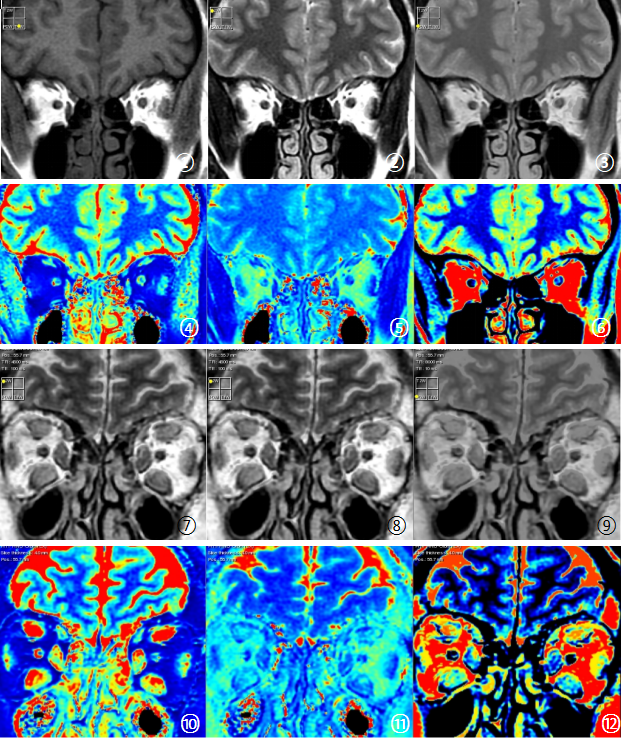

Figure1 Synthetic MRI images of experimental group and healthy controls

① to ⑥ are the schematic diagram of healthy controls synthetic MRI images, which are T1WI, T2WI, PDWI, T1MAPPING, T2MAPPING and PDMAPPING, respectively ⑦ -Synthetic MRI images of the experimental group were consistent with those of the healthy controls.